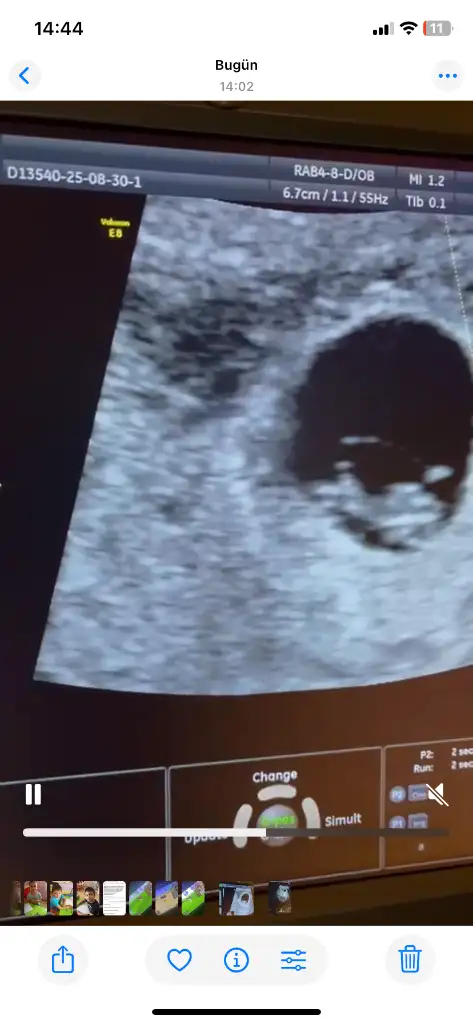

Çok merak ediyorum, karından bakıldı bu arada

• IMG_A56B3D3C-E51F-4F4F-9D58-475B83A21CA1.webp

IMG_A56B3D3C-E51F-4F4F-9D58-475B83A21CA1.webp

45,1 KB · Görüntüleme: 77

• IMG_69036796-489B-4BA1-A057-8DC900512DB2.webp

IMG_69036796-489B-4BA1-A057-8DC900512DB2.webp

108,8 KB · Görüntüleme: 104